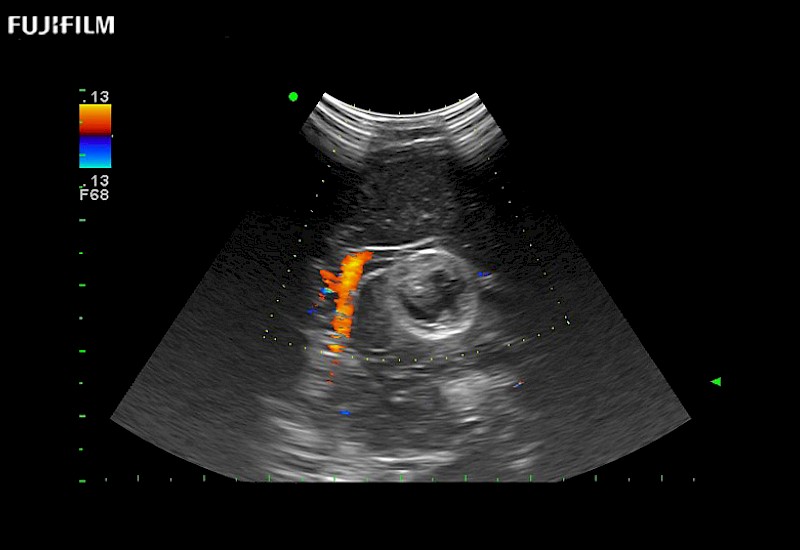

Smaller footprint (20mm) curved array transducer that is ideal for scanning during cranial guidance procedures.

Main Specifications: